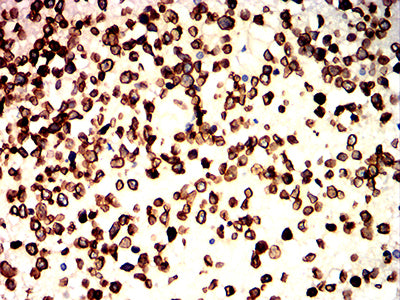

Immunohistochemical analysis of paraffin-embedded human ovarian cancer tissues using LMNB1 mouse mAb with DAB staining.